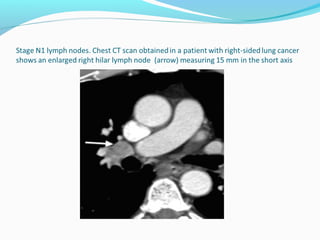

N1 - Nodes

N1-nodes are ipsilateral nodes within the lung up to

hilar nodes.

N1 alters the prognosis but not the management.

N1 - Nodes N1-nodesare ipsilateral nodes within the lung up to hilar nodes. N1 alters the prognosis but not the management.